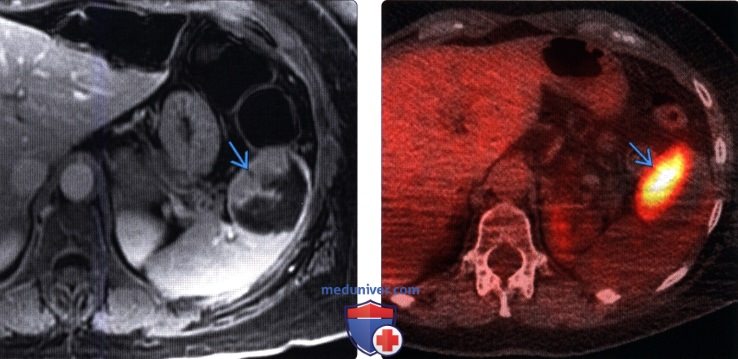

Интраренальная лоханка: рентгеновские снимки и примеры

Раздел: Фотоэссе